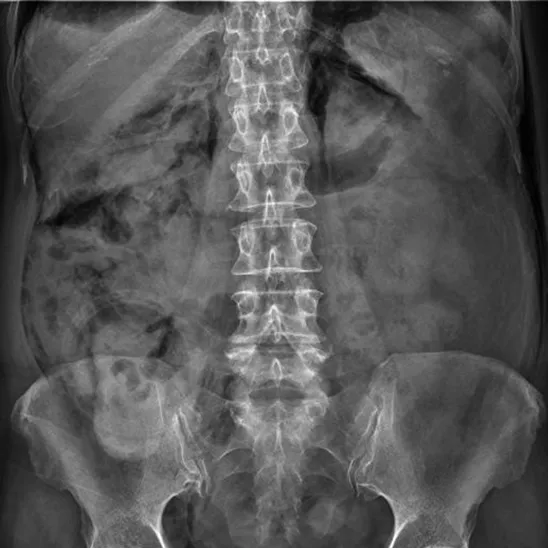

28세 여성이 자전거 사고 후 복통을 호소하며 응급실로 내원했다. 혈압 130/85 mmHg, 맥박 88회/분, 호흡수 15회/분, 체온 36.5℃로 측정되었다. 복부 진찰 결과 우측 상복부에 압통 및 경미한 반발압통이 관찰되었다. 복부 초음파 및 복부 CT 촬영 결과가 나왔다. 손상된 부위는 어디인가?

• 복부 X선, 복부 CT 상 신장 주위 retroperitoneal area에 저음영의 공기가 관찰되어 (perinephric air) 후복막 장기의 손상이 의심된다.